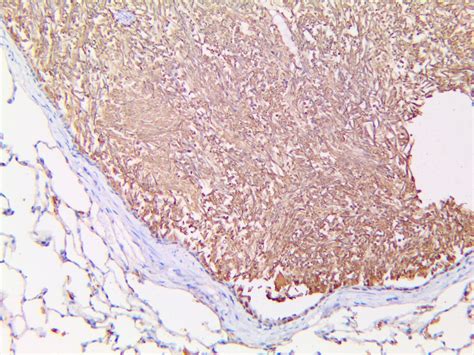

Treponema pallidum, often referred to as *T. pallidum*, is a bacterium responsible for causing syphilis, a sexually transmitted infection (STI) that can have severe health consequences if left untreated. Understanding the biology, transmission, symptoms, diagnosis, and treatment of *T. pallidum* is crucial for public health and individual well-being. This post delves into the intricacies of *T. pallidum* and its associated infection, syphilis.

*T. pallidum* is a spiral-shaped bacterium, known as a spirochete, which is highly motile and can invade various tissues in the human body. It is a member of the genus Treponema, which includes other pathogenic species like *T. carateum* and *T. pertenue*. *T. pallidum* is particularly notable for its ability to evade the host's immune system, making it a challenging pathogen to detect and treat.

Treponemal tests specifically detect antibodies against *T. pallidum*. These tests are more specific and include:

• Fluorescent Treponemal Antibody Absorption (FTA-ABS) test

• Treponema pallidum Particle Agglutination (TP-PA) test

• Enzyme Immunoassay (EIA) test

Treponemal tests are often used to confirm the diagnosis of syphilis, especially in cases where non-treponemal tests are inconclusive.